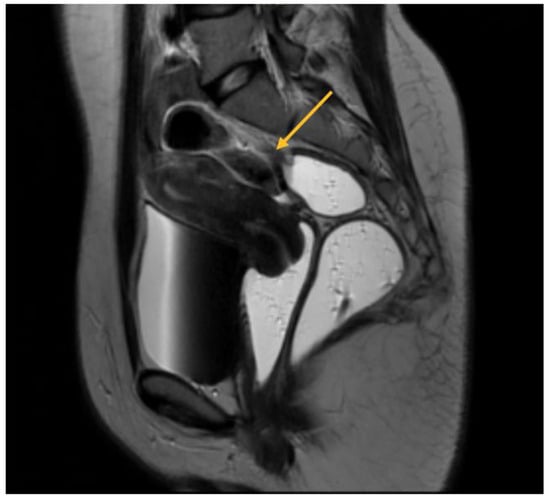

As will be elaborated upon in the forthcoming discussion section, the identification of parametrial lesions may prove more challenging in the absence of collaboration with a radiologist possessing specialized expertise in recognizing DIE lesions. The parametrial nodule manifests as a hypointense thickening or evidence of a mass with irregular contours situated in the posterior uterine region, as depicted in Figure 4 [16].

Figure 1. MRI aspect on T2 sagittal (a) Left endometrioma with left ovary adherent to the posterior uterine wall (b) Right endometrioma.